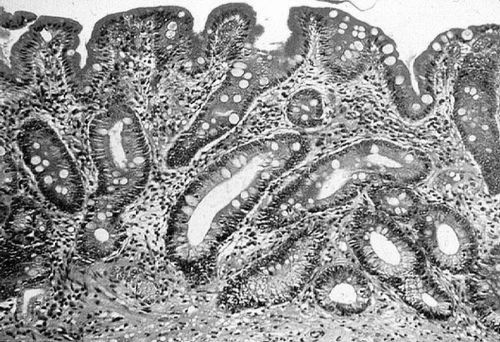

Виявляється патологія після дослідження біоптату слизової, яка проводиться в процесі ФГДС. У препараті виявляють характерні змінені клітини, які продукують сульфамуцін. Ця речовина здатна абсорбувати на собі канцерогени, які провокують розвиток онкології.

Також клітини змінюють склад своїх антигенів: з'являється раково-ембріональний антиген (свідоцтво зниження диференціювання клітин), підвищений рівень якого виявляють у крові. В результаті проведених досліджень виставляється діагноз, в формулюванні якого враховуються розміри і місце знаходження метаплазії, наприклад, вогнищева кишкова метаплазія слизової антрального відділу шлунка.